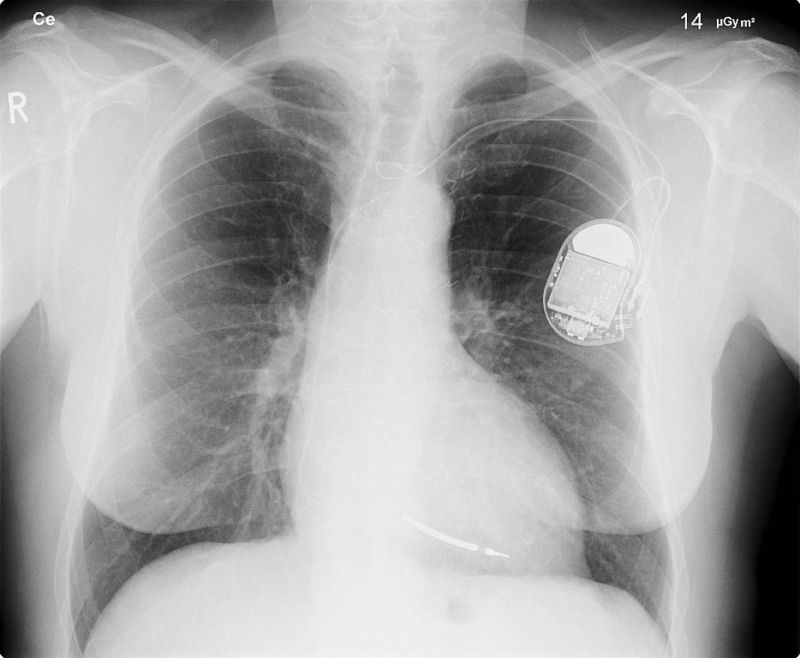

А речь идет о таких жизненно важных устройствах, как ритмоводители и дефибрилляторы (не те, что показывают в сериалах о врачах, другие). Это миниатюрные устройства, которые вживляются в тело человека для того, чтобы в моменты, когда сердце работает с проблемами, оно получало электрический сигнал, позволяющий «включить» обычный режим работы сердечной мышцы.

Если с таким гаджетом что-то случится, то его владельца ждут неминуемые проблемы, вплоть до летального исхода. Хуже всего то, что дефибрилляторы становятся все более «умными». Те из них, что выпускаются компанией Medtronic, оказались еще и уязвимыми для внешнего вмешательства.